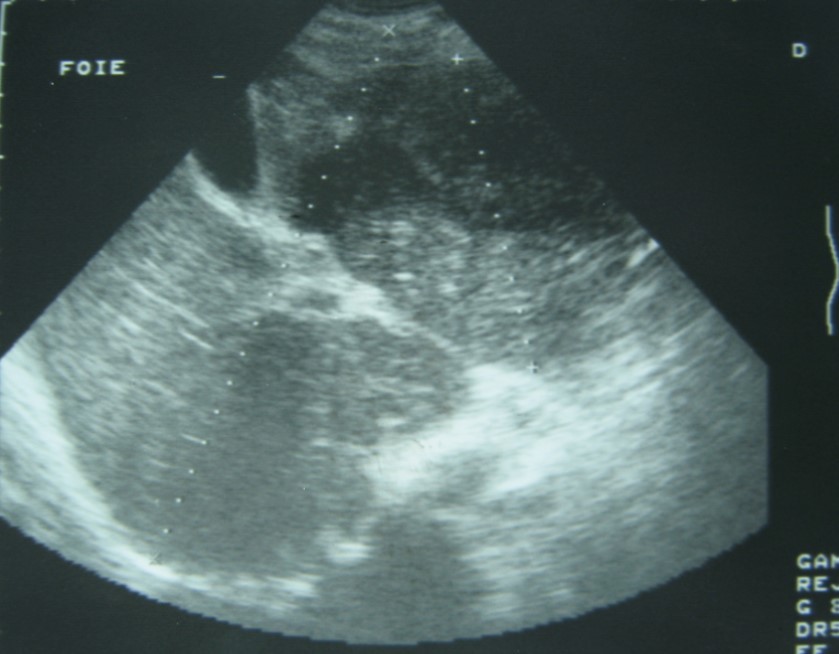

Laboratory analysis showed hemoglobin, 10.9 g/dL; white blood cell count, 9,800 cells/mm3, serum albumin, serum total bilirubin, alanine aminotransferase, aspartate aminotransferase, prothrombin time, hepatitis B surface antigen, and antibodies to hepatitis C, serum alpha-fetoprotein (AFP), carcinoembryonic antigen and carbohydrate antigen 19-9 (CA 19-9) were within normal range. Blood cultures were negative. Chest x-ray was normal. Ultrasound of abdomen showed a 10 cm hypoechogenic lesion in left liver (Figure 1). An abdominal CT showed a well-defined heterogeneous mass situated in his left hepatic lobe measuring 10 cm × 7 cm (Figure 2, Figure 3). The lesion featured central necrosis, a hyper-dense rim and a mild enrichment from the arterial phase in the CT, The diagnosis of primary hepatic tumor was suspected. An ultrasonography-guided needle biopsy of the liver was scheduled in order to rule out malignancy and to have a complete diagnosis. Cytology demonstrated a tuberculosis granuloma, acid-fast bacilli culture was positive (Figure 4). Anti-tuberculous therapy including isoniazid, rifampin, ethambutol, and pyrazinamide were prescribed. The patient completed the 6-month course of medication with success. The patient’s appetite and body weight were restored to previous levels. One year after the completion of treatment, the patient remained completely asymptomatic with disease free.

Figure 1.Ultrasonography showing a 10 cm hypoechoic lesion

Imaging is useful for diagnosis. Abnormal chest x-rays demonstrating pulmonary tuberculosis can help for diagnosis. Our patient presented with no evidence of active pulmonary disease and the ultrasonography showed a hypoechoic rim and solitary lesion. In theses cases, it is difficult to differentiate them from carcinoma 11.